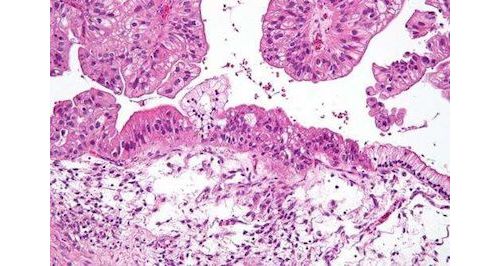

液体活组织切片通常指的是血液活体检测,需要从外周血液中采集肿瘤细胞材料用于检测。虽然来自非血液体液中的肿瘤细胞一直在细胞学检查中临床可用,但由于常规细胞病理学的敏感性低,在鉴别诊断中的使用有限。